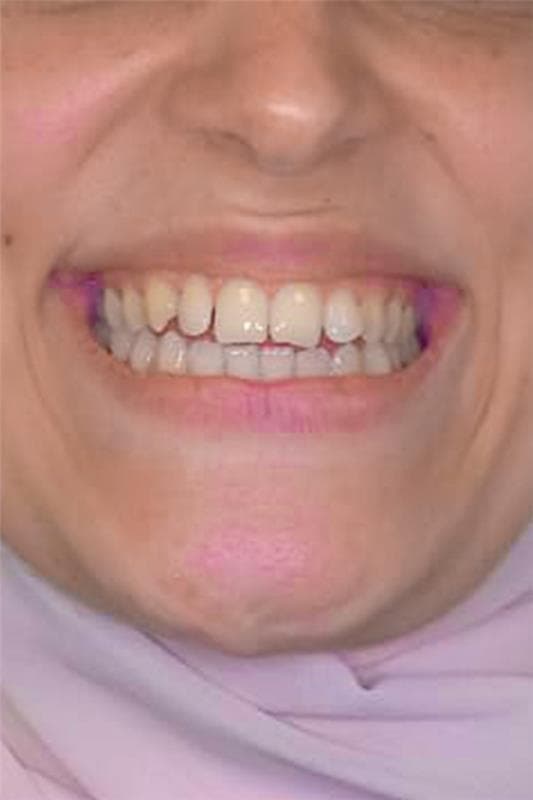

Spacing

Crowding

Protrusion

Bite Issues